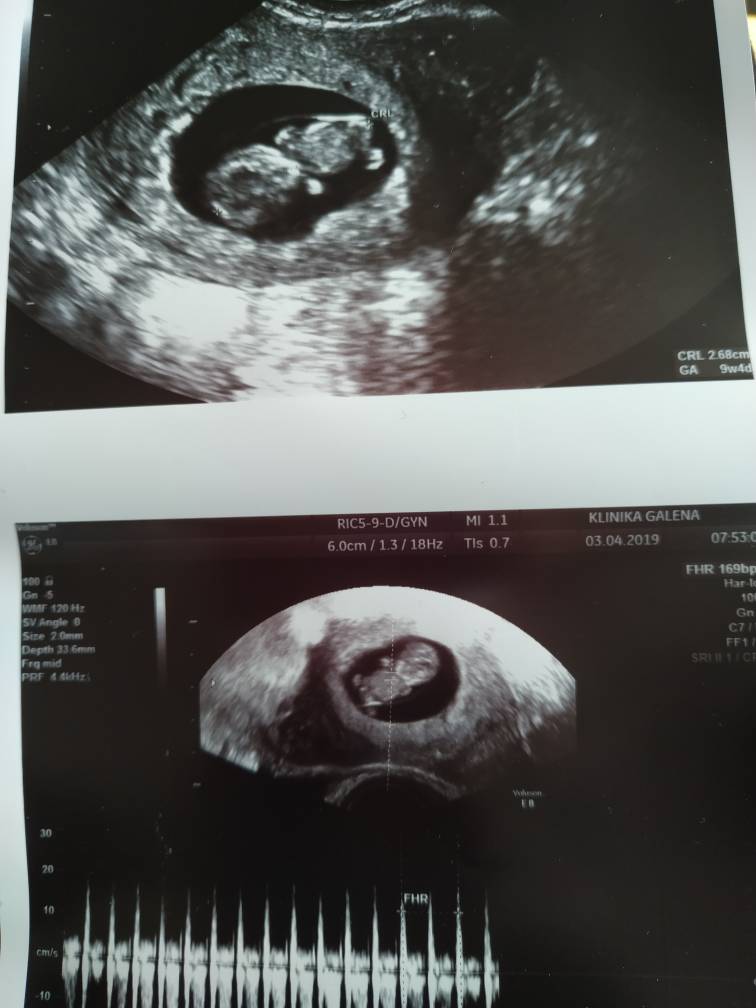

Jaki cudny maly ludzik!! To sa najpiekniejsze usg jak widac robaczka w całości. Gratuluję całym sercem. Dbajcie o siebie i rosnijcie zdrowo.Kochane jestem dzisiaj po USG, 19 prenatalne jestesmy najszczęśliwszymi rodzicami na świecie. Mimo kłótni wczoraj i wcześniej zapomnieliśmy o wszelkich żalu do siebie. Już nawet teściowa mnie wali. Mam dla kogo żyć i dbać o siebie. Dziękuję Wam za wsparcie idę świętować przy dobrym soku!Zobacz załącznik 958494